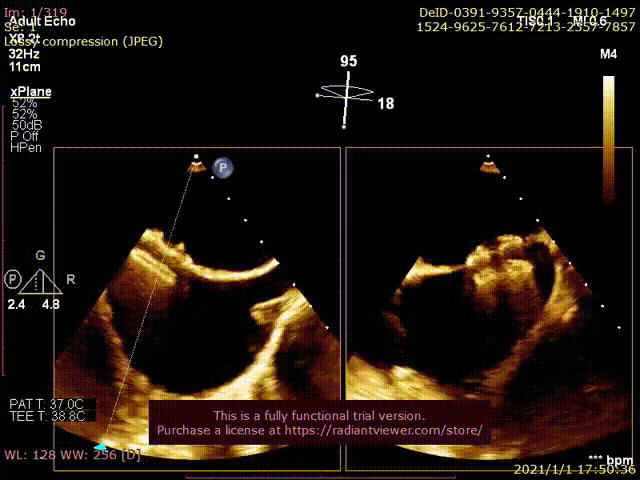

术后即刻分流器稳定,可见左向右分流束。

经胸超声可见分流器形态良好,无血栓

经胸超声可见左向右分流束